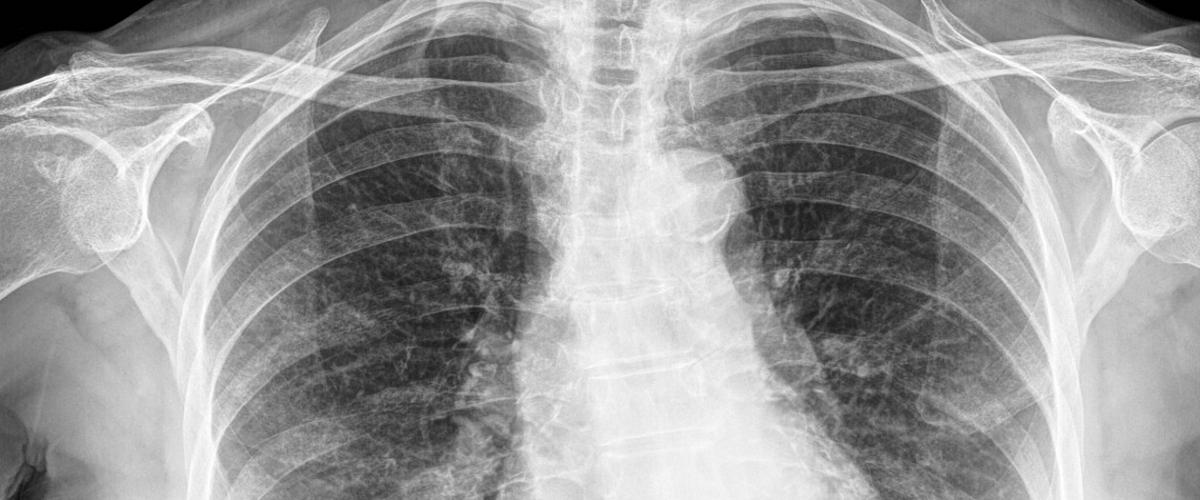

При этом у разных пациентов гипоксемия может сопровождаться различными симптомами. Например, у некоторых больных есть одышка, а у других нет. На этом основании исследователи предлагают разделить COVID-19 на два фенотипа — L и H. Они отличаются по ряду характеристик, включая вес легких и реакцию на кислород, и требуют разного лечения.

Легче всего отличить пациентов с L- и H-формами болезни можно с помощью компьютерной томографии. Авторы надеются, что эти данные позволят увеличить выживаемость пациентов с COVID-19.